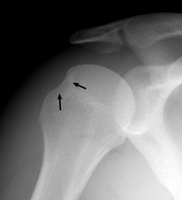

The Hill-Sachs fracture results from anterior dislocation of the humeral head and is located on the posterolateral aspect of the humeral head. 97 % of shoulder dislocations are anterior in direction. This fracture is produced when the humeral head strikes the inferior margin of the glenoid. The dislocation may also cause a Bankart fracture at the impact site on the glenoid. Anterior dislocations are produced by complex forces acting on the humerus, including abduction and external rotation.

A | AP radiograph of the shoulder. The arrows indicate the defect on the posterolateral aspect, corresponding to a Hill-Sachs fracture. |